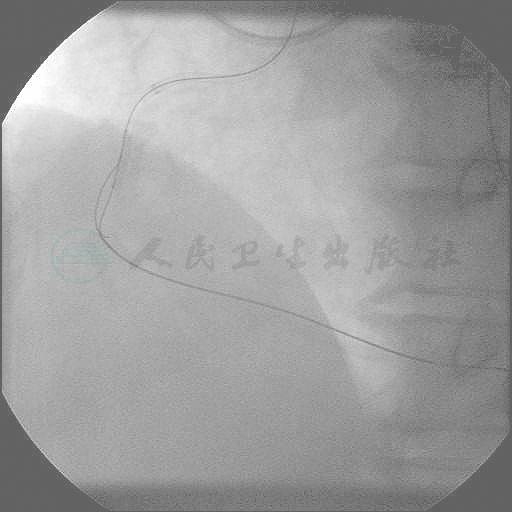

经右桡动脉、股动脉径路,选择经股动脉6F XB RCA指引导管,桡动脉行对侧造影,在微导管辅助下,先后尝试PT2MS、Pilot 150、Miracle 3、Conquest等导丝,但由于闭塞段较长,反复尝试,操控导丝造成多个假腔,最终未能进入真腔,正向未能成功开通RCA-CTO病变(图4)。

2周后,再次尝试开通右冠CTO病变。考虑前次PCI前向导丝技术失败且存在多个假腔,而患者LAD-RCA心外膜血管侧支较好,但经间隔支侧支不好,因此尝试逆向导丝技术。由于前次手术导致右桡动脉搏动不能触及,且考虑本次手术需要7F强支撑指引导管,因此选择双侧股动脉路径,选择7F动脉鞘。左冠指引导管选择7F EBU 3.5,右冠指引导管选择7F AL 1.0。左冠造影显示,经LAD心外膜血管到右冠侧支非常好(图5),经左冠状动脉指引导管送入Sion导丝及Corsair微导管,导丝逆向顺利到达RCA中段闭塞处,再交换Fielder XT导丝,反复尝试但导丝进入假腔(图6~图8)。再经右指引导管送入PT2MS导丝,经闭塞段近端正向进入假腔,先后送入1.25mm×10mm,2.0mm×20mm,2.5mm×15mm Sprinter Legend球囊于右冠近端假腔内扩张,再反复操控逆向导丝最终逆向进入前向球囊扩张的假腔通道并进入RCA近端管腔,再送入逆向导丝进入RCA指引导管(图9~图12)。逆向导丝由右冠指引导管拉出体外后,建立导丝轨道,沿此导丝送入微导管再交换为BMW导丝(图13、图14),球囊扩张后造影显示RCA前向血流通畅(图15、图16)。慢性闭塞血管长期失用性萎缩,冠状动脉造影常低估管腔直径,因此需要使用IVUS评估闭塞血管的真实管径,同时因为采用反向CART技术,近端血管存在大量夹层与假腔,不能过多和高压注射显影剂显示评估血管状况。本例患者进行了IVUS检查评估真实管腔直径,指导支架选择(图17、图18)。RCA血管远段到近段序贯植入3.0mm×30mm、3.5mm×30mm、3.5mm×30mm、4.0mm×30mm Resolute支架4枚(图19、图20),以12~14atm释放,再行3.5mm×15mm NC Sprinter高压球囊18~20atm后扩张(图21),术后行IVUS检查示支架膨胀良好(图22、图23),最终造影显示无残余狭窄,TIMI血管3级(图24、图25)。

图6 逆向导丝到达LAD远端